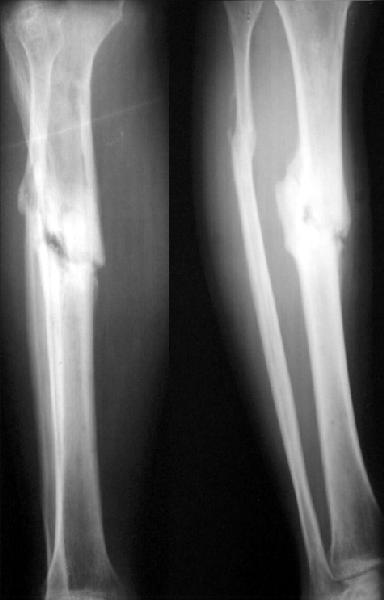

No hollow reamers and nails are still availble yet, so UTN 10 mm was used. After perQ osteotomy of the fibula i tried to open the canal, and the awl was passed to the distal fragment only after closed mobilization of the site to make some antecurvation. It resulted with some anterior translation of the distal fragment :( After impaction the nail was locked dynamically. Images attached. Comments/critics are

welcome.

get_image.jpg

16KB (17241 bytes)

I believe this nailed nonunion of the tibia shaft will likely go on to uneventful healing. Good job.

I'm not clear if you opened the fracture site and used an awl or if you used an awl through the nail entry site. The latter is preferred although often difficult and sometimes impossible.

Today the case was criticized at the week clinical report for the antecurvation deformity... Unhappily our vice-director tries to prove that such a malalignment is of great clinical importance.

Yes, nailing was closed, the canal was opened through the nail entry site.

I would expect the deformity of the case of nailed tibia shaft nonunion (slight apex posterior and slight posterior translation) to be of no definite and small theoretical clinical importance.